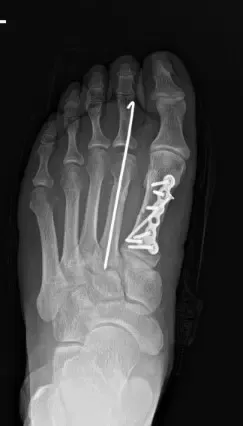

Una radiografía del pie derecho confirmó fracturas en el primer y segundo metatarsiano.

La fijación definitiva se logró usando placas y tornillos de titanio.

Las imágenes fluoroscópicas confirmaron alineación anatómica y fijación estable.

Fijación interna postoperatoria con placa y tornillos de una fractura del primer metatarsiano.